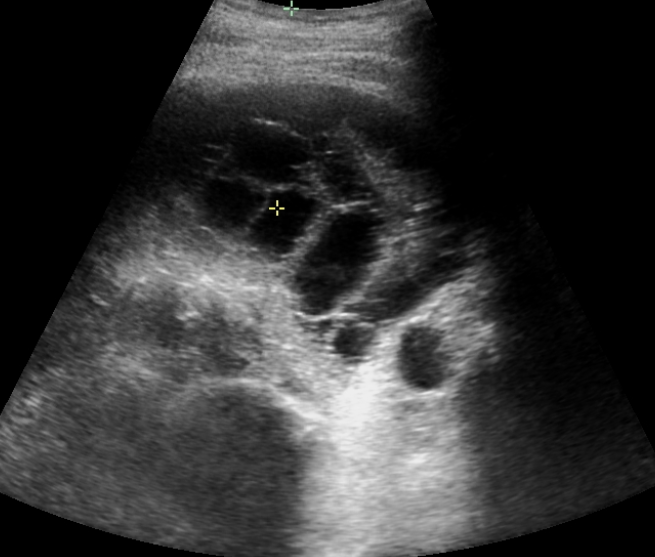

Rawatan utama empyema adalah bergantung kepada organisma yang menyebabkan penyakit tersebut. Kebiasaanya pesakit akan dimulakan dengan ubatan intravena antibiotic spektrum luas sehingga organisma dapat dikesan dan rawatan tersebut akan diubah suai. Untuk sebarang  rawatan ‘’nanah” yang terdapat di dalam badan pesakit, prinsip utama rawatannya adalah pengeluaran nanah tersebut; dan ini termasuklah empyema. Doktor akan membuat ultrasound dada dan  selepas mengenalpasti tempat dan bius setempat diberikan,   tiub dada akan dimasukkan untuk mengeluarkan nanah tersebut.

Kadang kala, tiub dada tidak dapat mengeluarkan kesemua nanah tersebut disebabkan nanah tersebut telah membentuk banyak poket atau septasi; dan tiub hanya mngeluarkan nanah dari satu ruang sahaja. Jika ini terjadi; rawatan intrapleural alteplase dan pulmozyme dapat dimulakan jika tiada kontra-indikasi.